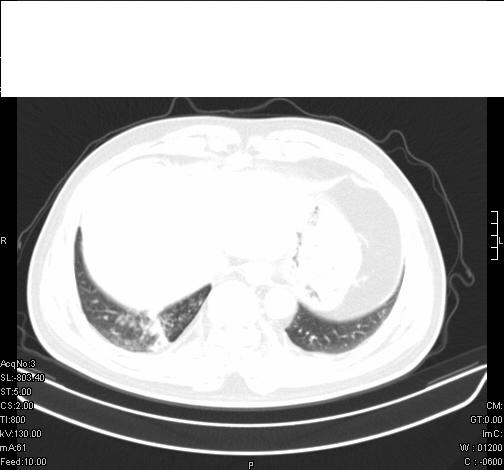

标题: CT6685:右肺阻塞性炎症,增强CT。 [打印本页]

标题: CT6685:右肺阻塞性炎症,增强CT。

前几天,发了患者的平扫片,患者抗炎一周后增强扫描。右中叶病灶吸收明显,但下叶病灶未见明显吸收。右肺门可见结节影,看来凶多吉少

右肺下叶散在的斑片状致密影,下叶支气管变窄。考虑:右肺慢性炎症。

右肺下叶支气管壁不规则增厚,右肺下叶有斑片状影分布。考虑右肺中央型肺癌伴右肺下叶阻塞性改变。建议支纤镜检查。平扫比增强较好显示了病变情况。

既然抗炎治疗有效,可继续治疗;右肺下叶支气管管腔狭窄,管壁增厚,右下肺见斑片状高密度影,右侧主支气管后见结节影(淋巴结?),肺癌不能排出。